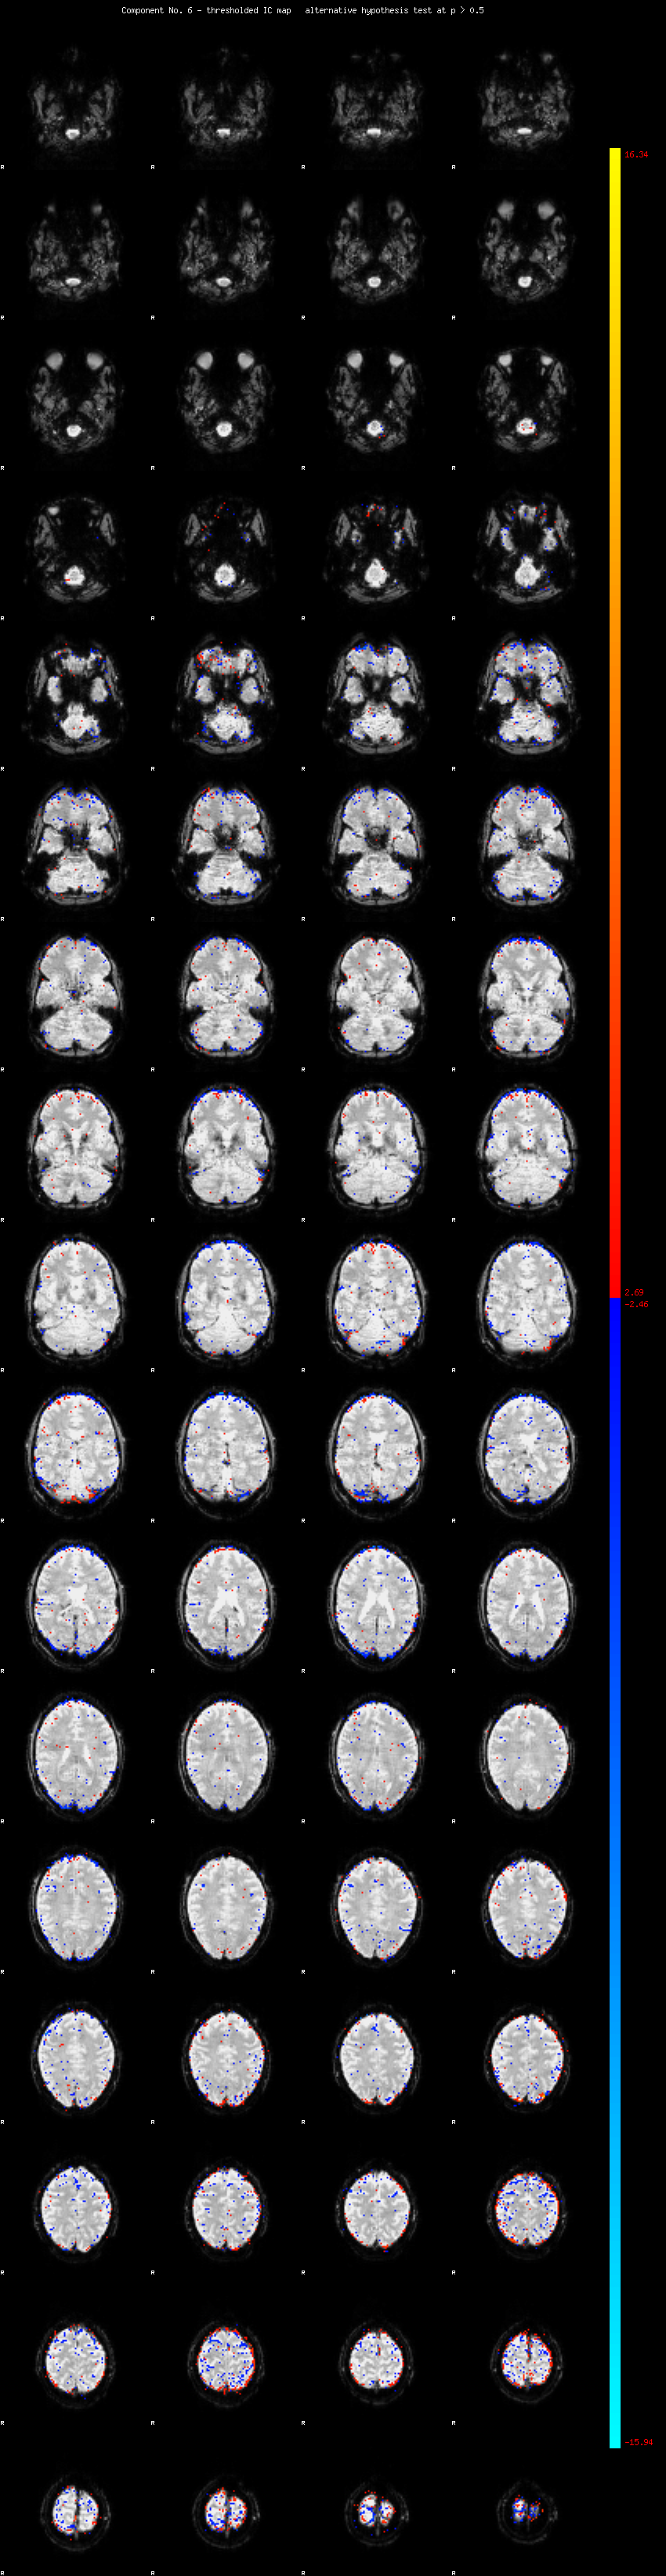

MELODIC Component 6

2.60 % of explained variance;     1.72 % of total variance